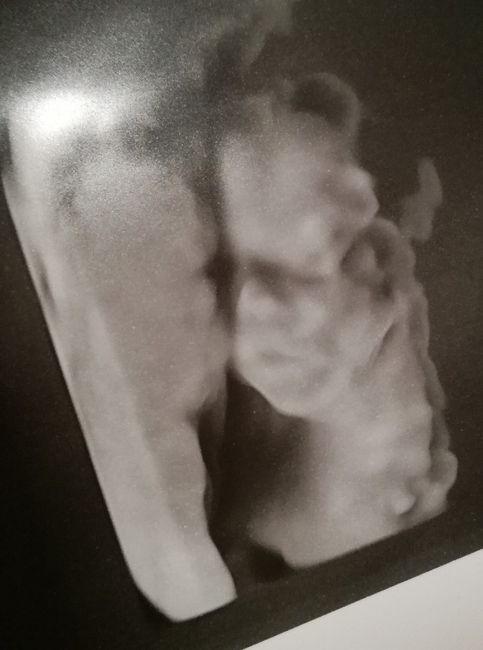

Mamme di ottobre 2019

Da Deaa , Il 29 Maggio 2019 alle 21:11

Salve ragazze! Chi mi fa compagnia? Che l'avventura abbia inizio!!! Sono emozionatissima!!! ...